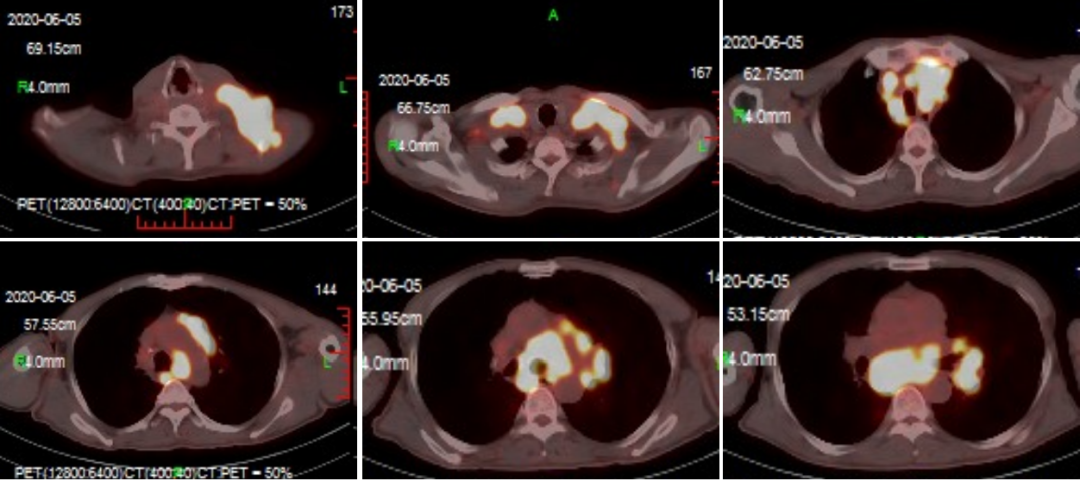

2020年8月26日,我院胰腺肿瘤MDT团队(胰腺外科、肿瘤内科、肝肿瘤外科、放疗科、介入科、病理科、内镜中心、医学影像科、核医学科、超声科等学科共同参与)利用午...